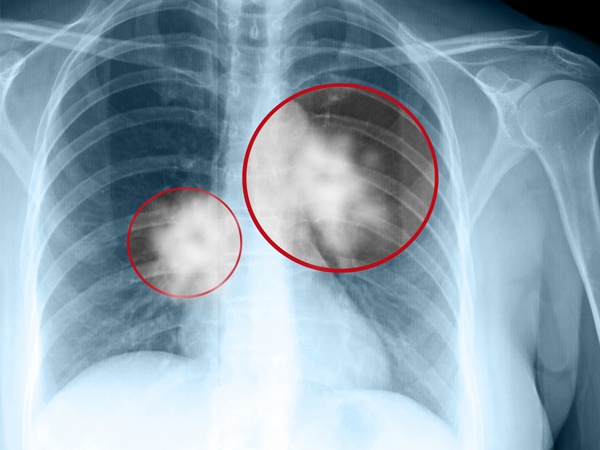

Số lượng người bị ung thư phổi không hề ít. Mỗi năm số người tử vong vì ung thư phổi nhiều hơn ung thứ vú, ung thư ruột già hoặc ung thư tuyến tiền liệt. Căn bệnh này ảnh hưởng nhiều nhất đến người già. Trong đó 81% người bị ung thư phổi đã trên 60 tuổi. |